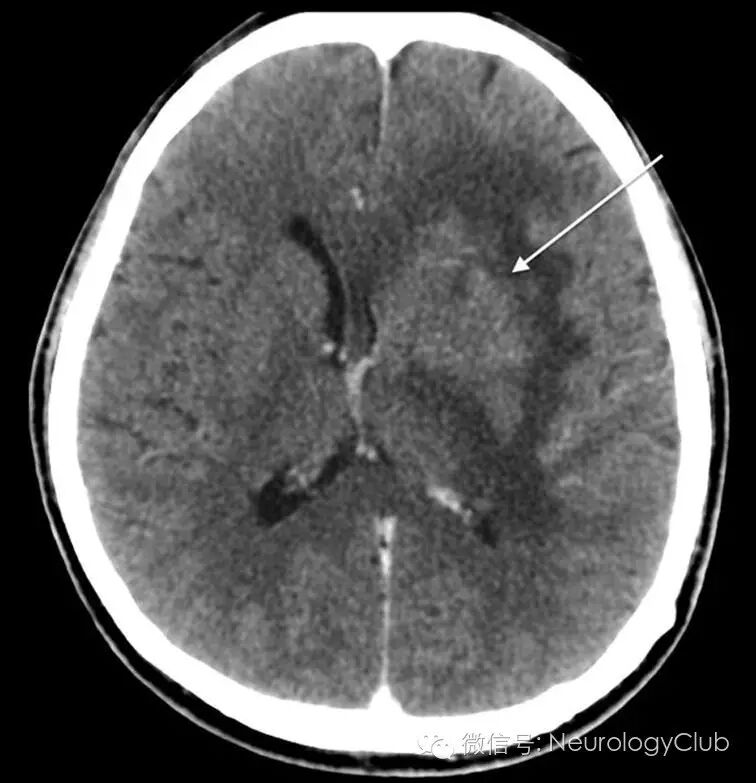

随后的MRI证实位于左侧基底节区的一较大的不均匀强化肿块,颞叶,岛叶和直回后部均有累及,占位效应存在(图2)。右侧额叶和左侧延髓也有局灶性强化。MRS提示部分区域Cho,NAA和乳酸峰升高。

(图2:起初的头颅MRI。T1WI[A],T1增强[B],T2WI[C]和FLAIR[D]证实左侧基底节区的一较大的不均匀强化肿块[箭],颞叶,岛叶和直回后部均有累及,占位效应存在